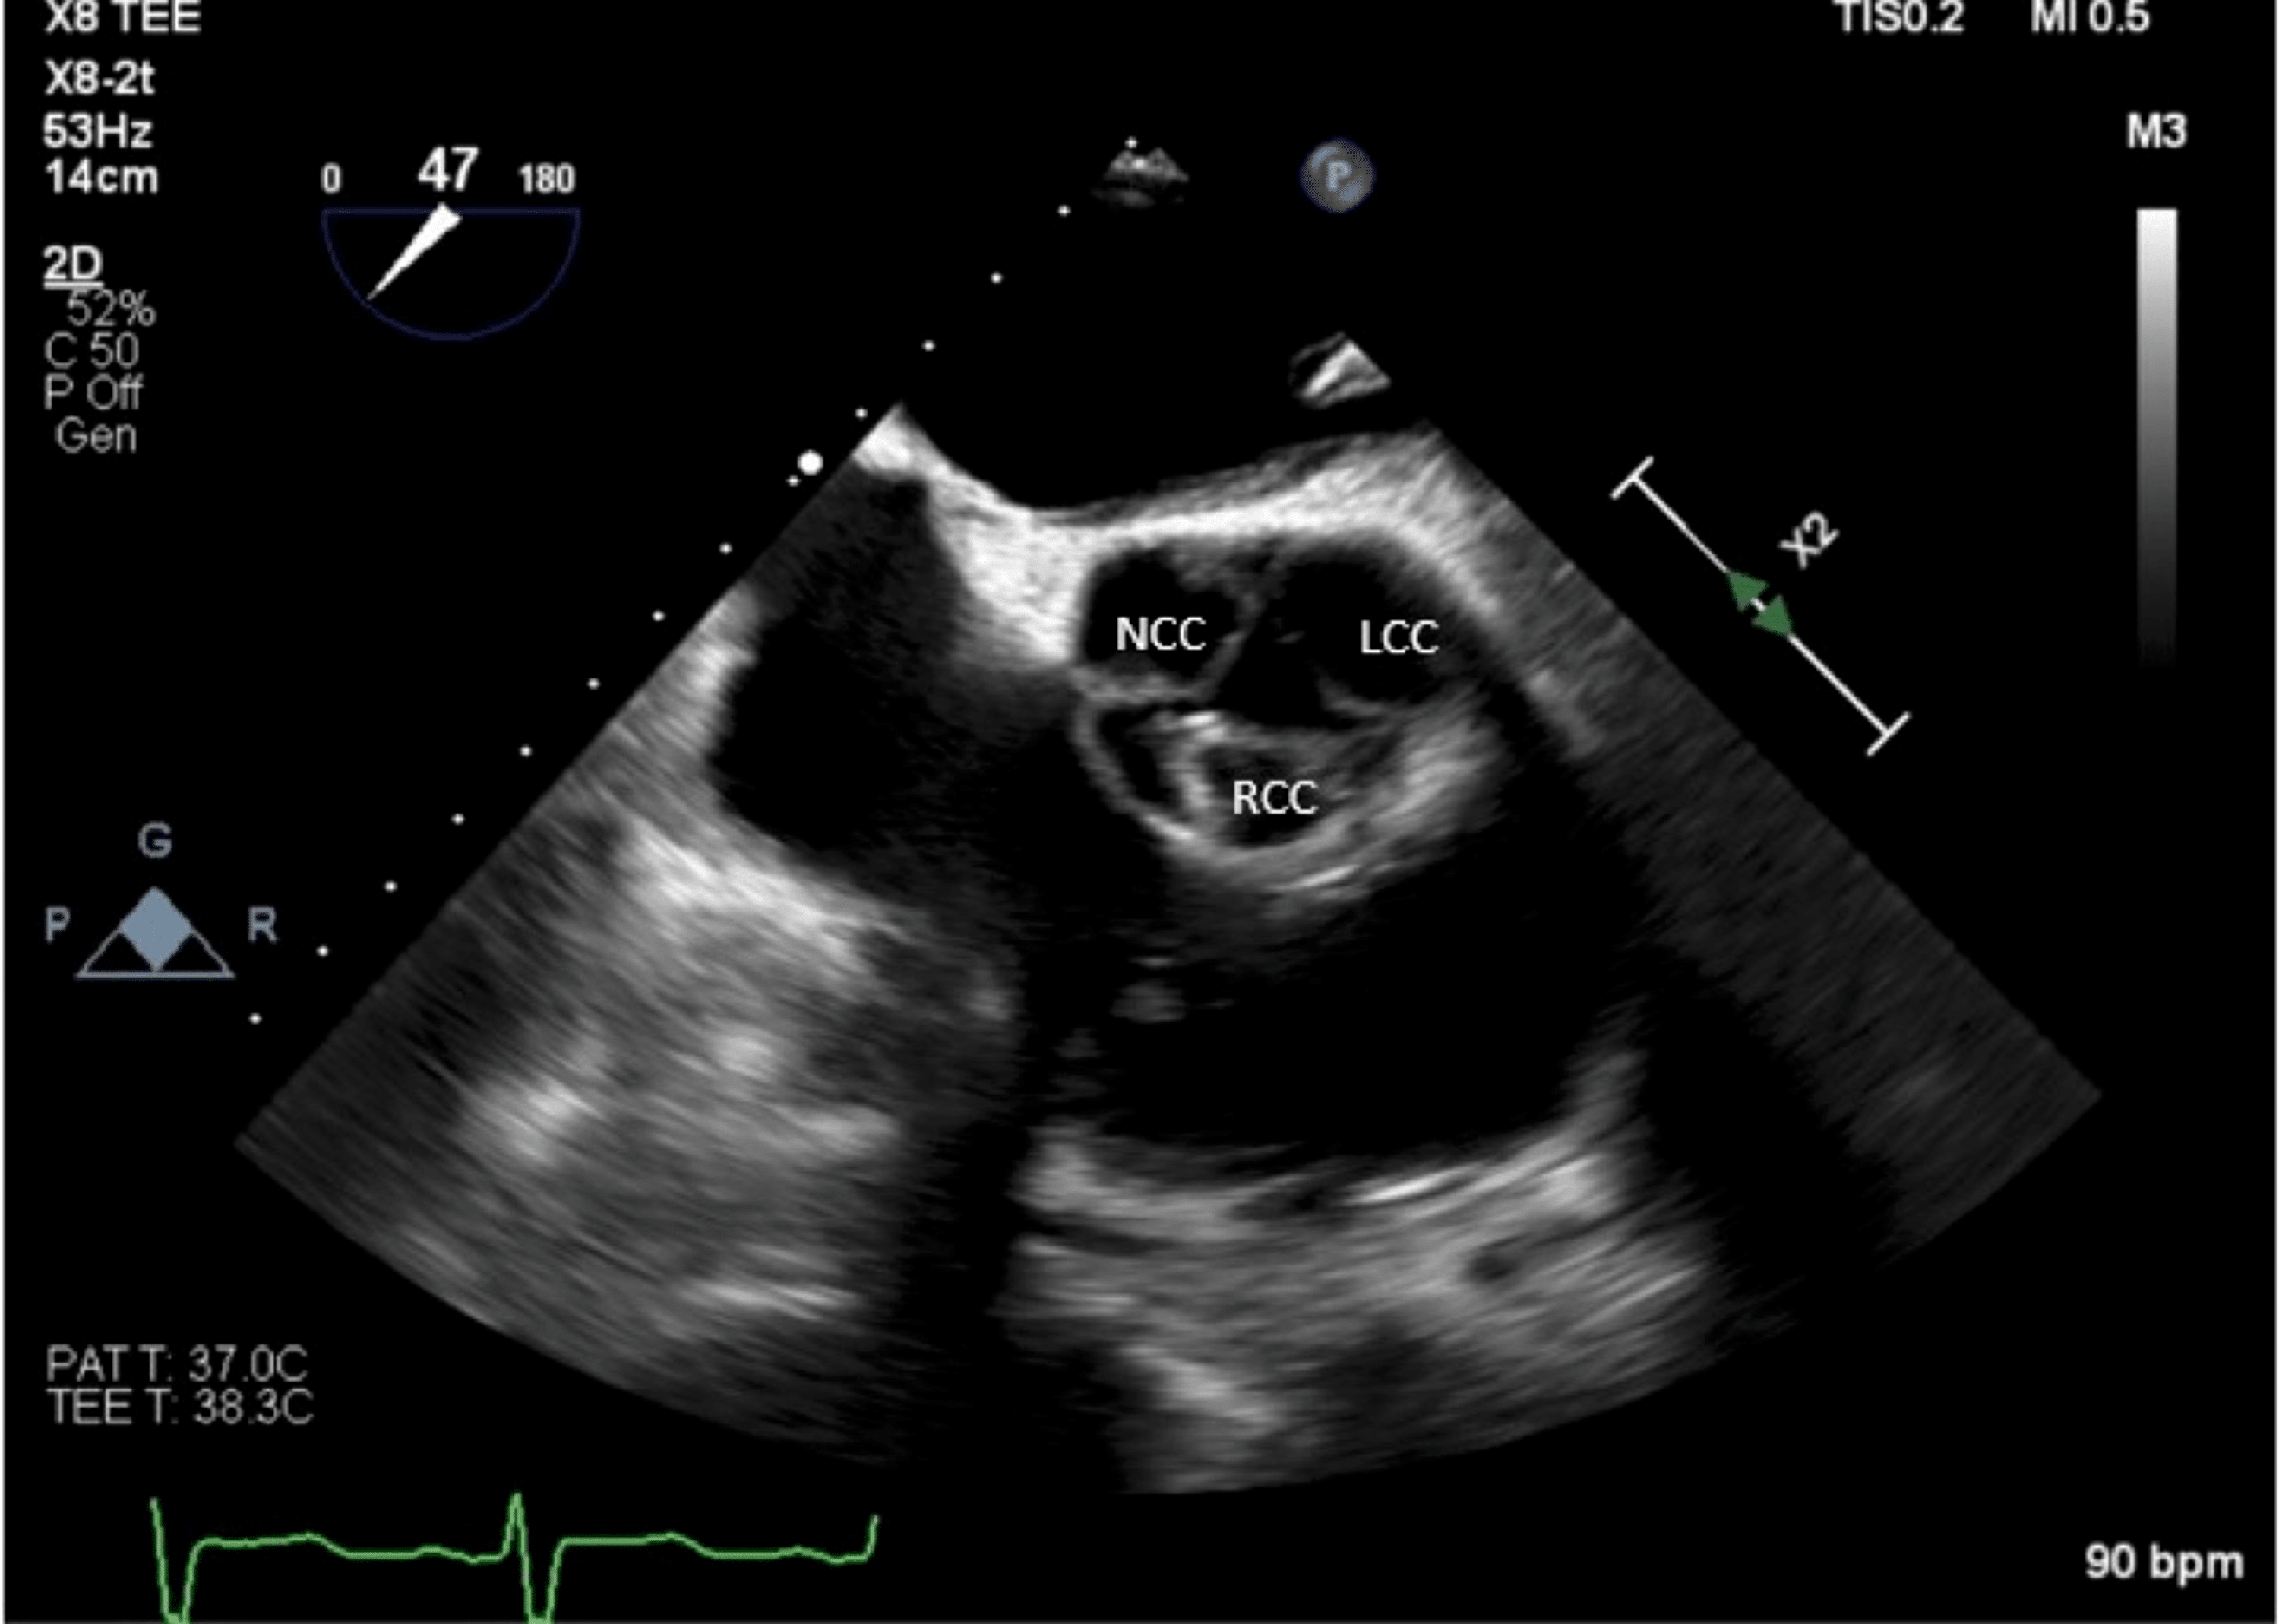

Cureus Prosthetic Valve Infective Endocarditis Secondary to Neisseria Movement Artifact At Diastole Coronary ct angiography is a novel noninvasive imaging technology that provides a unique view of cardiac and coronary artery pathologies. Cardiac gating or ecg gated angiography in ct is an acquisition technique that triggers a scan during a specific portion of the cardiac cycle. The precorrection image (a) shows an artifact in the lad (arrow) due to the acquisition band. Movement Artifact At Diastole.

An Unusual Etiology of Aortic Insufficiency A Case Report Cureus Movement Artifact At Diastole Often this technique is conveyed to. Cardiac gating or ecg gated angiography in ct is an acquisition technique that triggers a scan during a specific portion of the cardiac cycle. Coronary ct angiography is a novel noninvasive imaging technology that provides a unique view of cardiac and coronary artery pathologies. However, motion artifact can impair delineation of the coronary artery. Movement Artifact At Diastole.